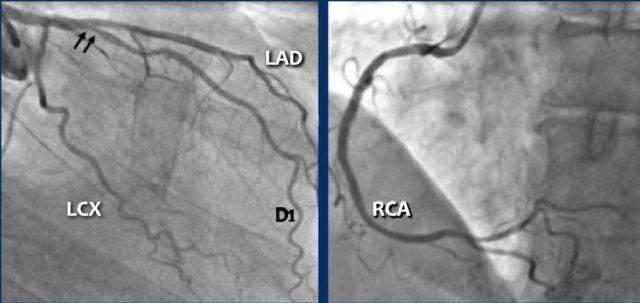

The ICA shows some wall irregularities to a maximum of 30% stenosis in

the proximal LAD.

The D1 shows 50% stenosis at the origin (black arrows). The LCX shows some wall

irregularities with no in-stent restenosis.

The RCA shows minimal wall irregularities, no in-stent restenosis.

This case also shows that CTA is limited in case of calcium and it can

overestimate the actual luminal stenosis.